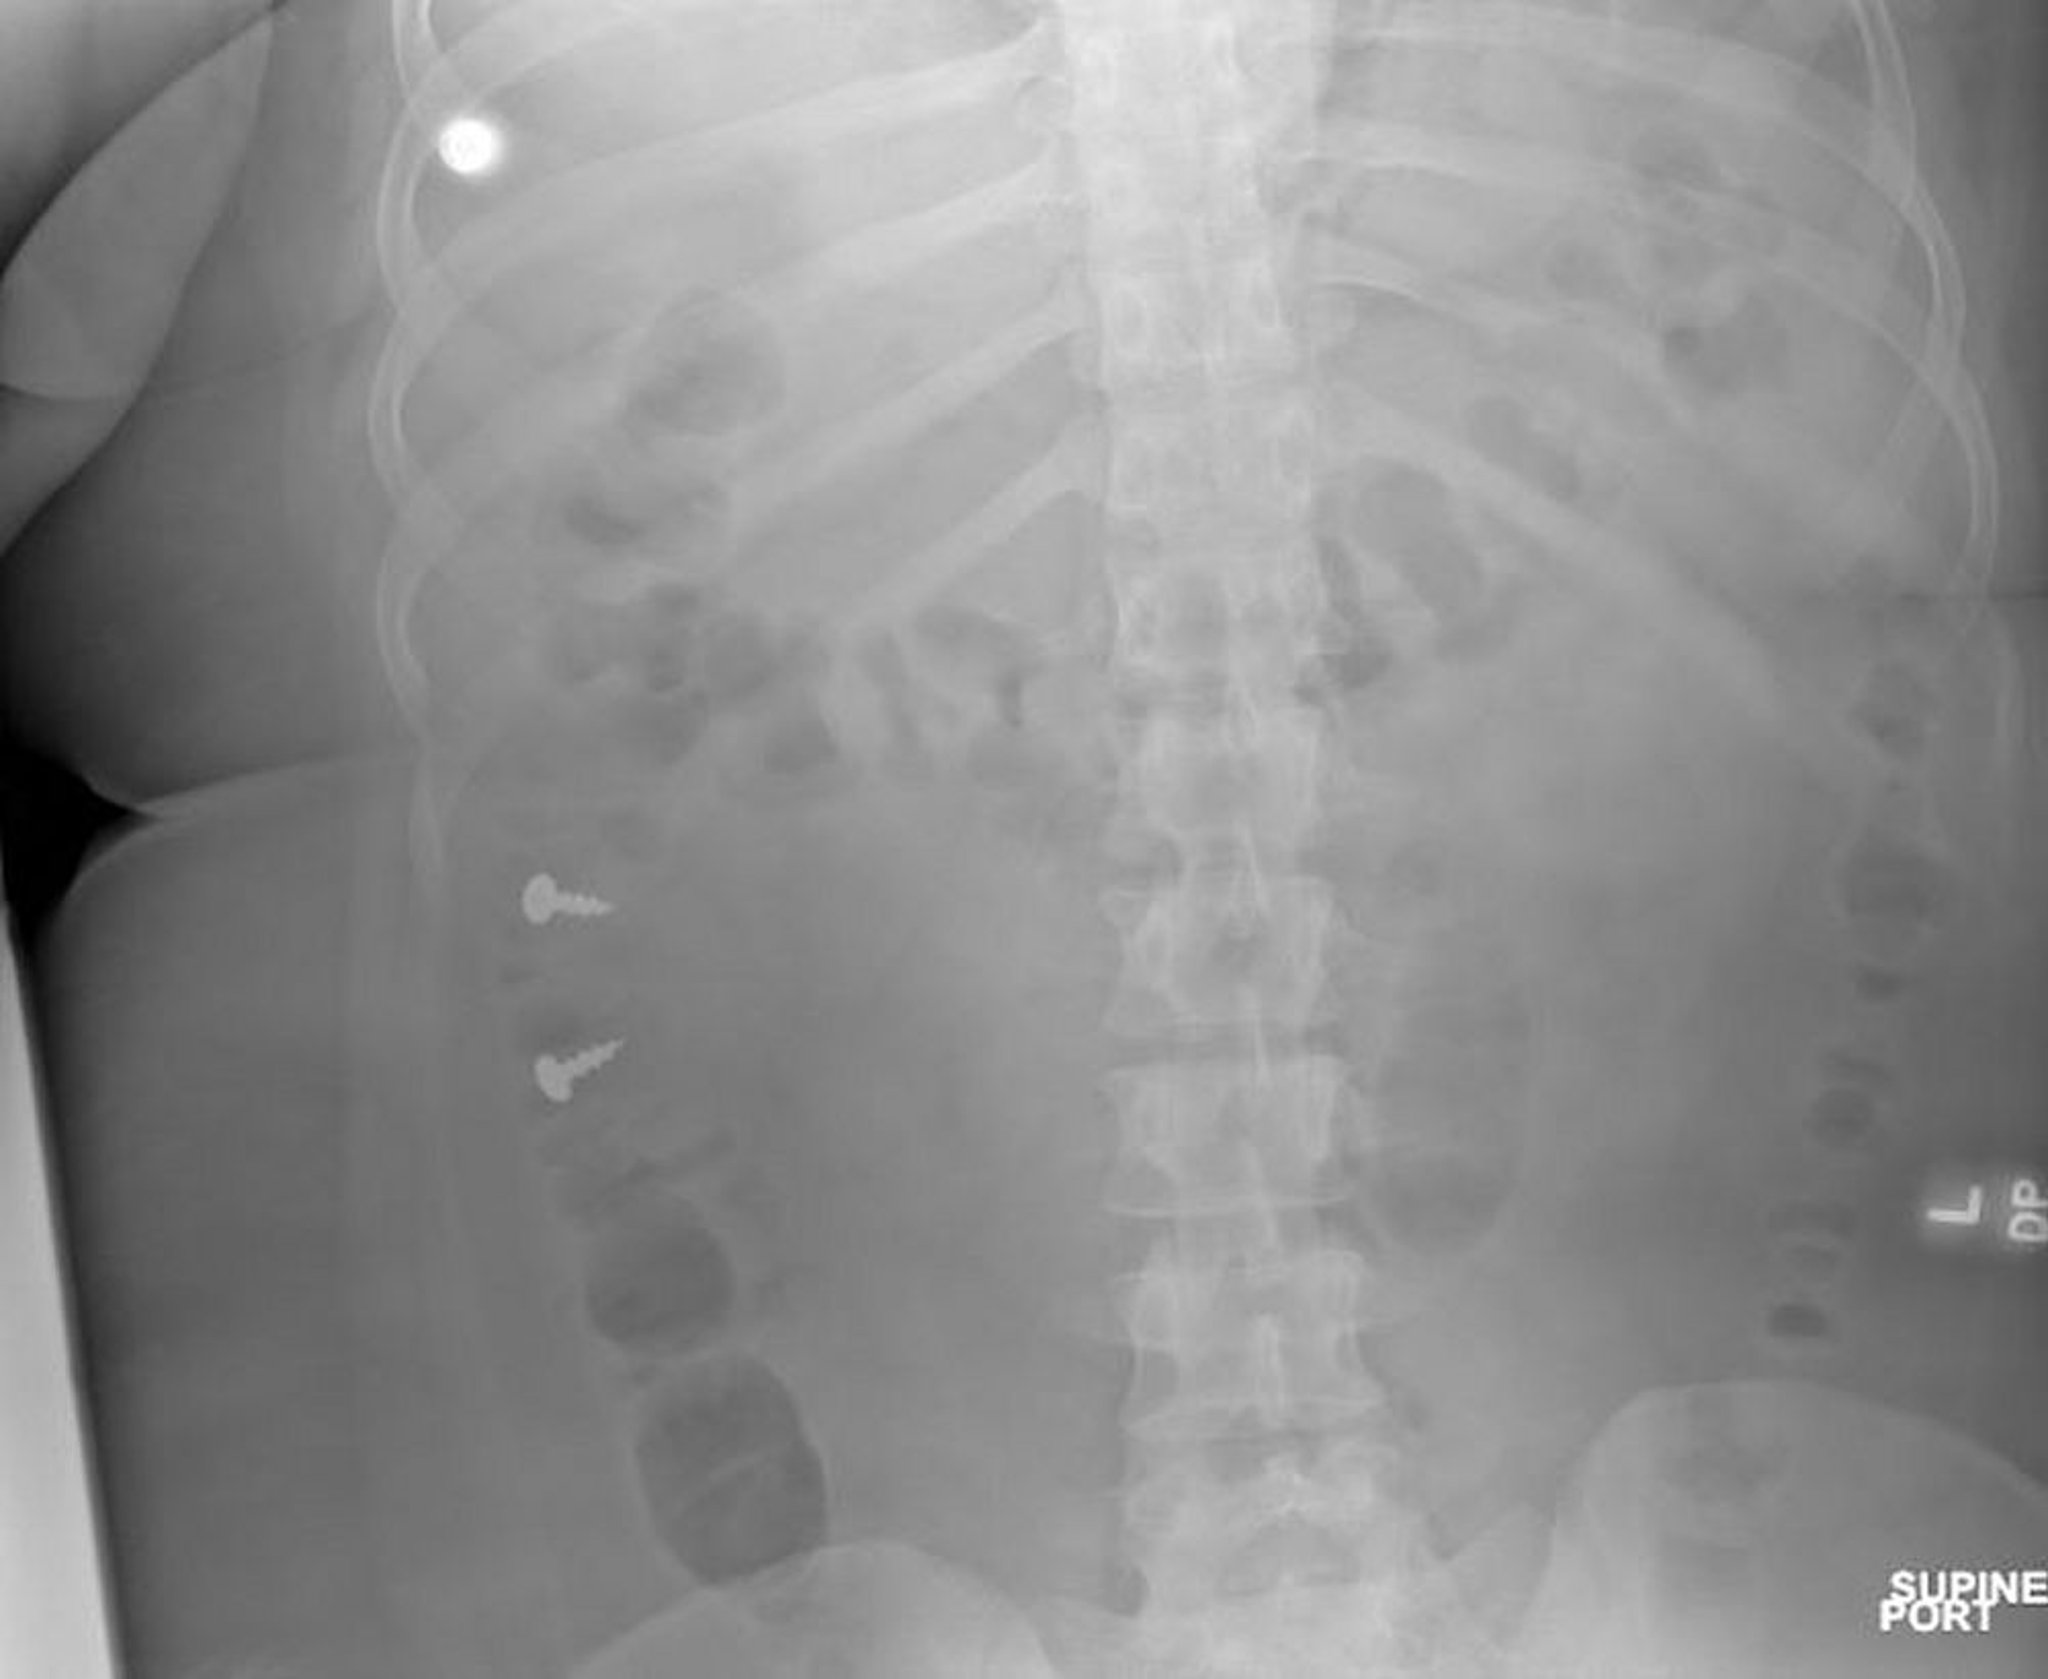

Tornillos en el colon (radiografía)

Image courtesy of Zubair Malik, MD.